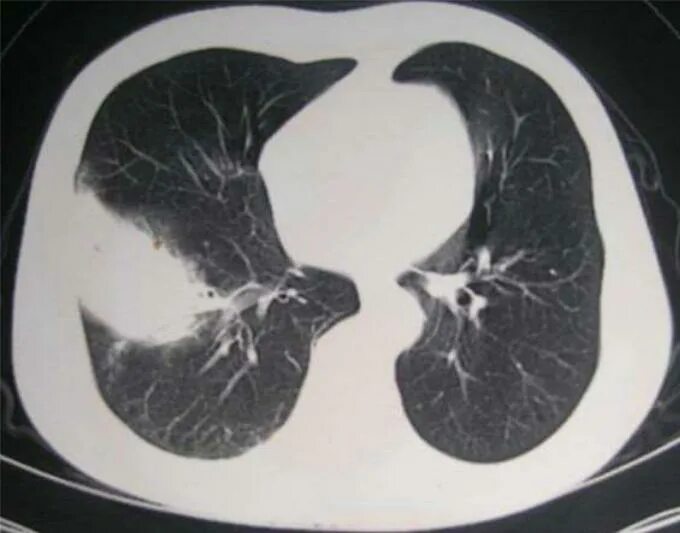

Как выглядит пневмония на кт